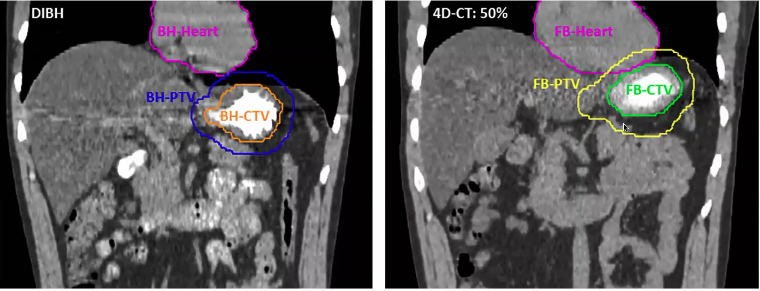

Lymphoma radiation, dose, local palliation, CTV

Follicular lymphoma, R-CHOP Chemotherapy, DLBCL, nodular lymphoma, post treatment scans, testicular lymphoma, photons vs. electrons, target volumes, dose, side effects, paranasal lymphoma, elderly, multiple myeloma, bone mets,